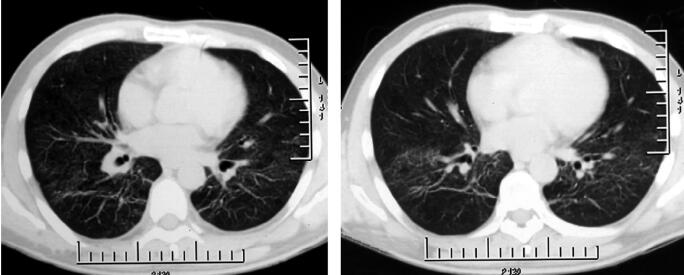

7.胸部影像学:胸部CT示双肺点状高密度影,磨玻璃样改变(图1)。

图1

重要的检查结果有两项:①静脉血淋巴细胞百分比增高,CRP、ESR增高;②胸部影像学示双肺多发浸润影;结合患者的病史和体格检查结果,进一步支持感染性疾病——社区获得性肺炎(community acquired pneumonia,CAP)的诊断,但目前病原学尚不明确。